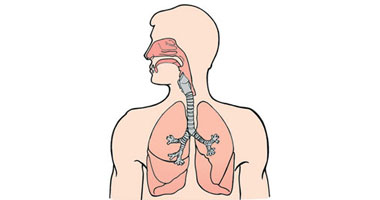

وظيفة جهاز التنفس:

في جهاز التنفس يحدث تبادل للغازات بين الجسم والبيئة.

يأخذ جهاز التنفس الاكسجين من البيئة ويطلق اليها ثاني اكسيد الكربون.

اعضاء جهاز التنفس:

فتحة التنفس(الانف) ,انابيب التنفس(القصبة الهوائية والشعب الهوائية),الرئتان والحجاب الحاجز.

عملية التنفس:

عملية التنفس من العمليات الأساسية لجسم الإنسان، فهي تمده بالأكسجين اللازم للجسم وتخلصه من ثاني أكسيد الكربون.

اهم الاعضاء في جهاز التنفس: